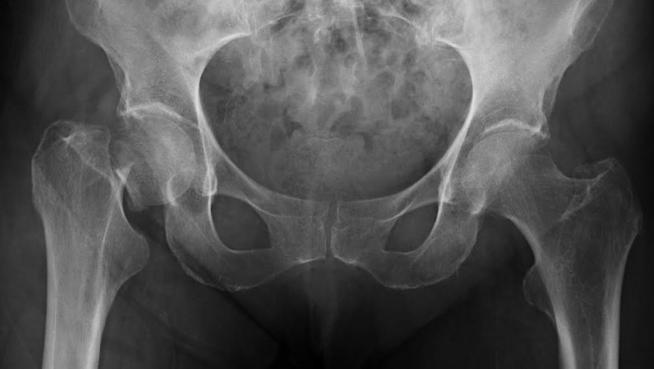

En segundo lugar, la osteoporosis es una enfermedad silenciosa en sus etapas iniciales, lo que significa que muchas mujeres no son conscientes de que tienen la enfermedad hasta que experimentan una fractura. Las fracturas osteoporóticas, especialmente las fracturas de cadera, columna vertebral y muñeca, son eventos catastróficos que pueden tener graves consecuencias para la salud y la calidad de vida. Las fracturas de cadera, en particular, son especialmente peligrosas, ya que se asocian con una alta tasa de morbilidad y mortalidad. Estas fracturas pueden causar discapacidad funcional, limitar la movilidad y aumentar el riesgo de complicaciones médicas graves, como neumonía y tromboembolismo pulmonar.